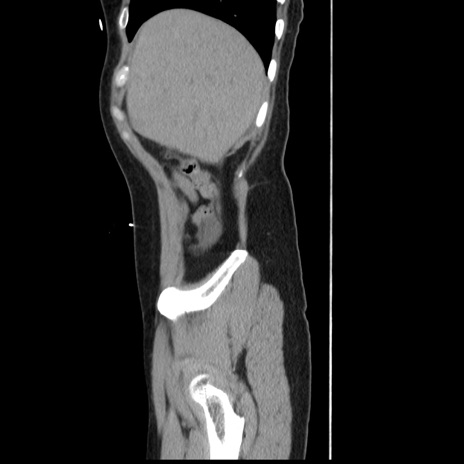

症例10(矢状断像)

【症例】 50歳代女性

【主訴】 腹痛

【現病歴】前日生レバーを食べた。今朝に排便あり。 昼前に突然発症の腹痛を生じ、当院救急外来を受診した。

【既往歴】 子宮筋腫にてで子宮全摘後

【身体所見】 意識清明、腹部:平坦、軟、下腹部やや左を中心に圧痛・反跳痛あり、筋性防御あり

【データ】WBC 7800、CRP 0.07